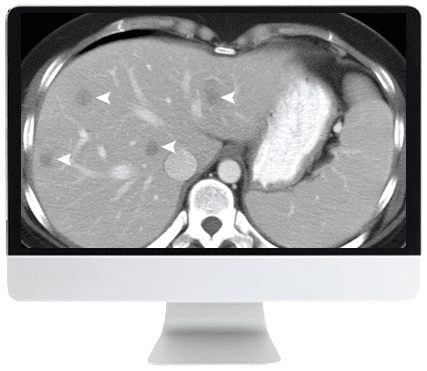

ARRS SAR Disease-Focused Panels: Cancer Imaging and Reporting Guidelines 2021 (CME VIDEOS) is an on-demand digital course developed by abdominal radiologists with subspecialty expertise in various cancer types. This course presents multidisciplinary consensus-based guidelines on imaging hepatocellular, pancreatic, ovarian, and prostatic cancers, along with the 2019 Bosniak classification for cystic renal masses. These standardized protocols support diagnosis, treatment, and surveillance using CT and MRI modalities.

• LI-RADS Treatment Response Algorithm: Unequivocal Updates — M. Mendiratta-Lala

• Describe hepatocellular carcinoma and pancreatic adenocarcinoma CT and MRI findings post-therapy.